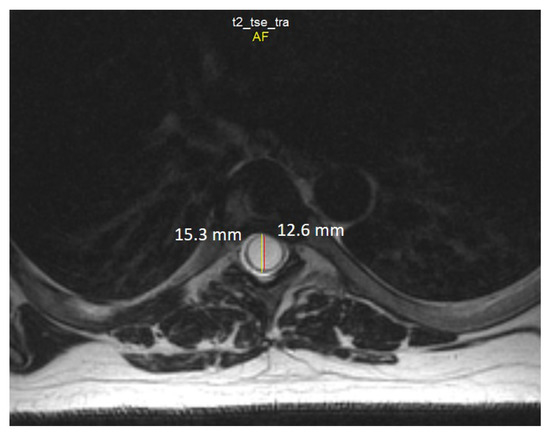

Chiari 1 Malformation (CM1) is classically defined as a caudal displacement of the cerebellar tonsils through the foramen magnum into the spinal cord. Modern imaging techniques and experimental studies disclose a different etiology for the development of CM1, but the main etiology factor [...] Read more.

Chiari 1 Malformation (CM1) is classically defined as a caudal displacement of the cerebellar tonsils through the foramen magnum into the spinal cord. Modern imaging techniques and experimental studies disclose a different etiology for the development of CM1, but the main etiology factor is a structural defect in the skull as a deformity or partial reduction, which push down the lower part of the brain and cause the cerebellum to compress into the spinal canal. CM1 is classified as a rare disease. CM1 can present with a wide variety of symptoms, also non-specific, with consequent controversies on diagnosis and surgical decision-making, particularly in asymptomatic or minimally symptomatic. Other disorders, such as syringomyelia (Syr), hydrocephalus, and craniocervical instability can be associated at the time of the diagnosis or appear secondarily. Therefore, CM1-related Syr is defined as a single or multiple fluid-filled cavities within the spinal cord and/or the bulb. A rare CM1-related disorder is syndrome of lateral amyotrophic sclerosis (ALS mimic syndrome). We present a unique clinical case of ALS mimic syndrome in a young man with CM1 and a huge singular syringomyelic cyst with a length from segment C2 to Th12. At the same time, the clinical picture showed upper hypotonic-atrophic paraparesis in the absence of motor disorders in the lower extremities. Interestingly, this patient did not have a disorder of superficial and deep types of sensitivity. This made it difficult to diagnose CM1. For a long time, the patient’s symptoms were regarded as a manifestation of ALS, as an independent neurological disease, and not as a related disorder of CM1. Surgical treatment for CM1 was not effective, but it allowed to stabilize the course of CM1-related ALS mimic syndrome over the next two years. Full article